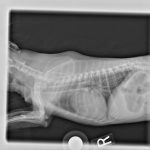

While X-rays allow us to see inside your pet so that we can better diagnose and treat him or her, they have limitations. A technique known as fluoroscopy allows us to overcome some of the shortcomings of traditional X-rays which capture one moment in time. Imagine X-rays, only in motion! This technique is creating new options in interventional radiology, minimally-invasive fracture repair, and tracheal stent repair for our patients at Oakland Veterinary Referral Services.

What is Fluoroscopy?

Fluoroscopy is a technique that uses low doses of continuous X-rays transmitted through the area of concern onto a fluorescent screen. These X-rays create a real-time moving image of structures within our patients’ bodies. This allows us to capture images, monitor procedures, and even manipulate the video as we work. Continue…